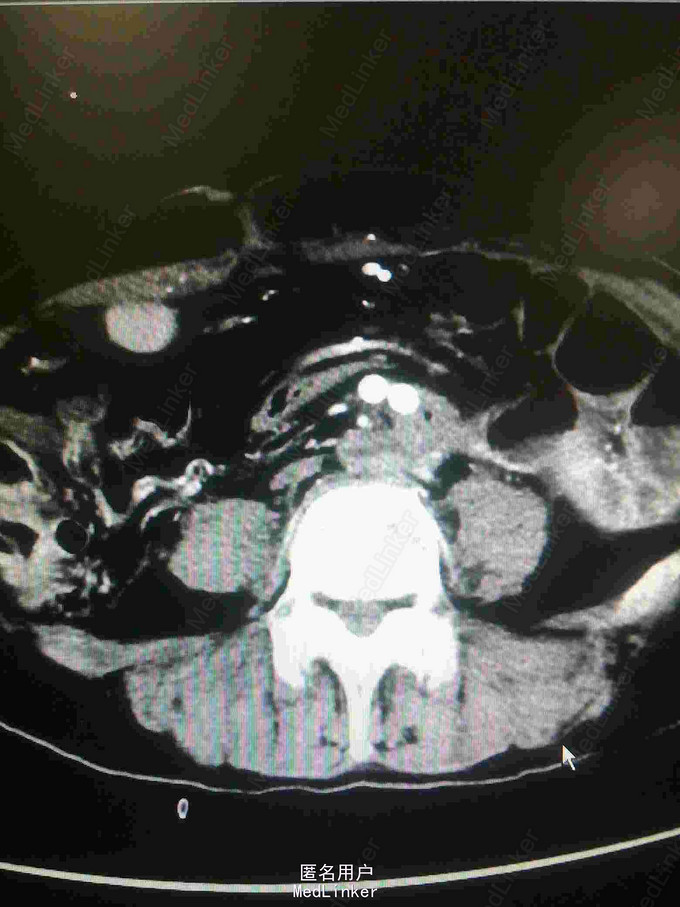

主诉:腰腹痛7月,加重一周。 病史:七月前发热后开始出现腰腹痛,呈持续性撕裂样痛,伴腹胀,症状反复。一周前腹痛症状加重。

体查:下腹部可触及搏动性包块。 辅助检查:腹部CT:腹主动脉假性动脉瘤并血栓形成,腰5椎体受侵蚀。血培养:沙门氏菌。

诊断:沙门氏菌感染性腹主动脉假性动脉瘤 处理:急诊行腹主动脉瘤切除人工血管置换术,术后予美罗培南抗感染8周,续以左氧氟沙星口服。